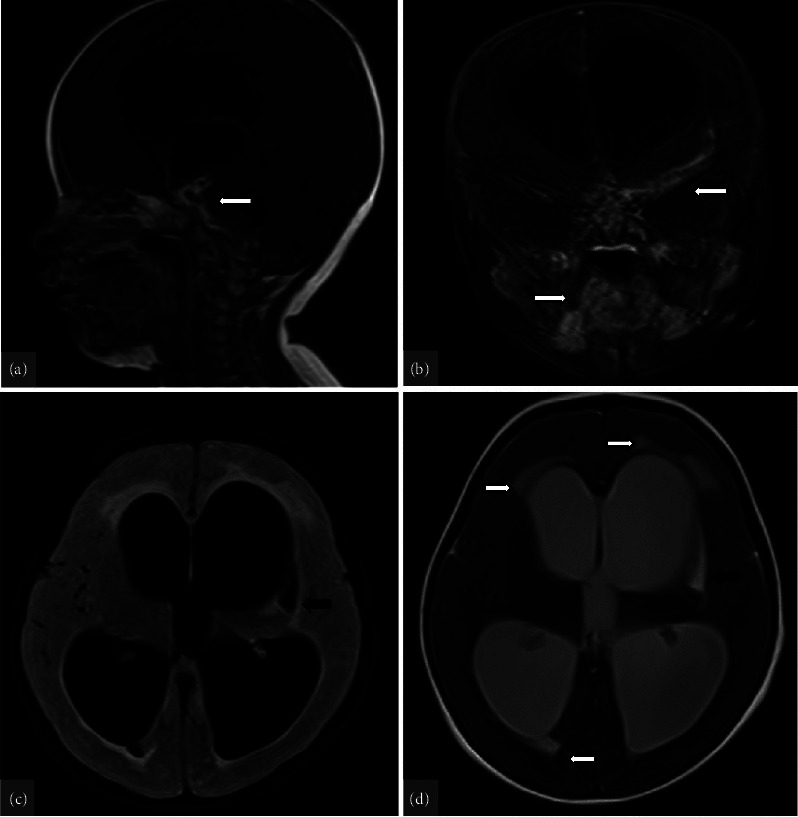

结核性脑膜炎(TBM)是一种严重的结核病,可导致很高的发病率和死亡率,尤其是在延误诊断和治疗的情况下。在本病例报告中,一名 9 个月大的女童因持续呕吐和局灶性抽搐入院。检查发现她右侧偏瘫。脑部影像学检查显示,她的脑膜呈强结节状强化、脑积水、左侧基底节低密度病变、动脉狭窄和血管炎以及陈旧性缺血性损伤。患者最初被诊断为急性缺血性中风,接受了阿司匹林和抗癫痫药物治疗。尽管进行了初步治疗,但患者的病情仍不见好转,于是进行了进一步诊断。结果发现了 TBM 诊断。该病例强调了将 TBM 视为神经系统症状的可能病因的重要性,尤其是在冠状病毒病 2019(COVID-19)大流行期间,严重急性呼吸系统综合征冠状病毒 2(SARS-CoV-2)感染和儿童多系统炎症综合征(MIS-C)的神经系统并发症病例中也可能出现类似症状。

Tuberculous meningitis (TBM) is a serious form of TB disease that can result in high morbidity and mortality, particularly if there are delays in diagnosis and treatment. In this case report, a 9-month-old girl was admitted with persistent vomiting and focal seizures. On examination, she was found to have a right-side hemiparesis. Brain imaging showed intense nodular leptomeningeal enhancement, hydrocephalus, a hypolucent lesion in the left basal ganglia, arterial stenosis and vasculitis, and an old ischemic insult. The patient was initially diagnosed with an acute ischemic stroke and was treated with aspirin and antiepileptic drugs. The patient's condition failed to improve despite initial treatment, leading to further diagnostic procedures. The results uncovered a diagnosis of TBM. The case highlights the importance of considering TBM as a possible cause of neurological symptoms, especially during the coronavirus disease 2019 (COVID-19) pandemic where similar symptoms can be present in cases of neurological complications of severe acute respiratory syndrome coronavirus 2 (SARS-CoV-2) infection and multisystem inflammatory syndrome in children (MIS-C).